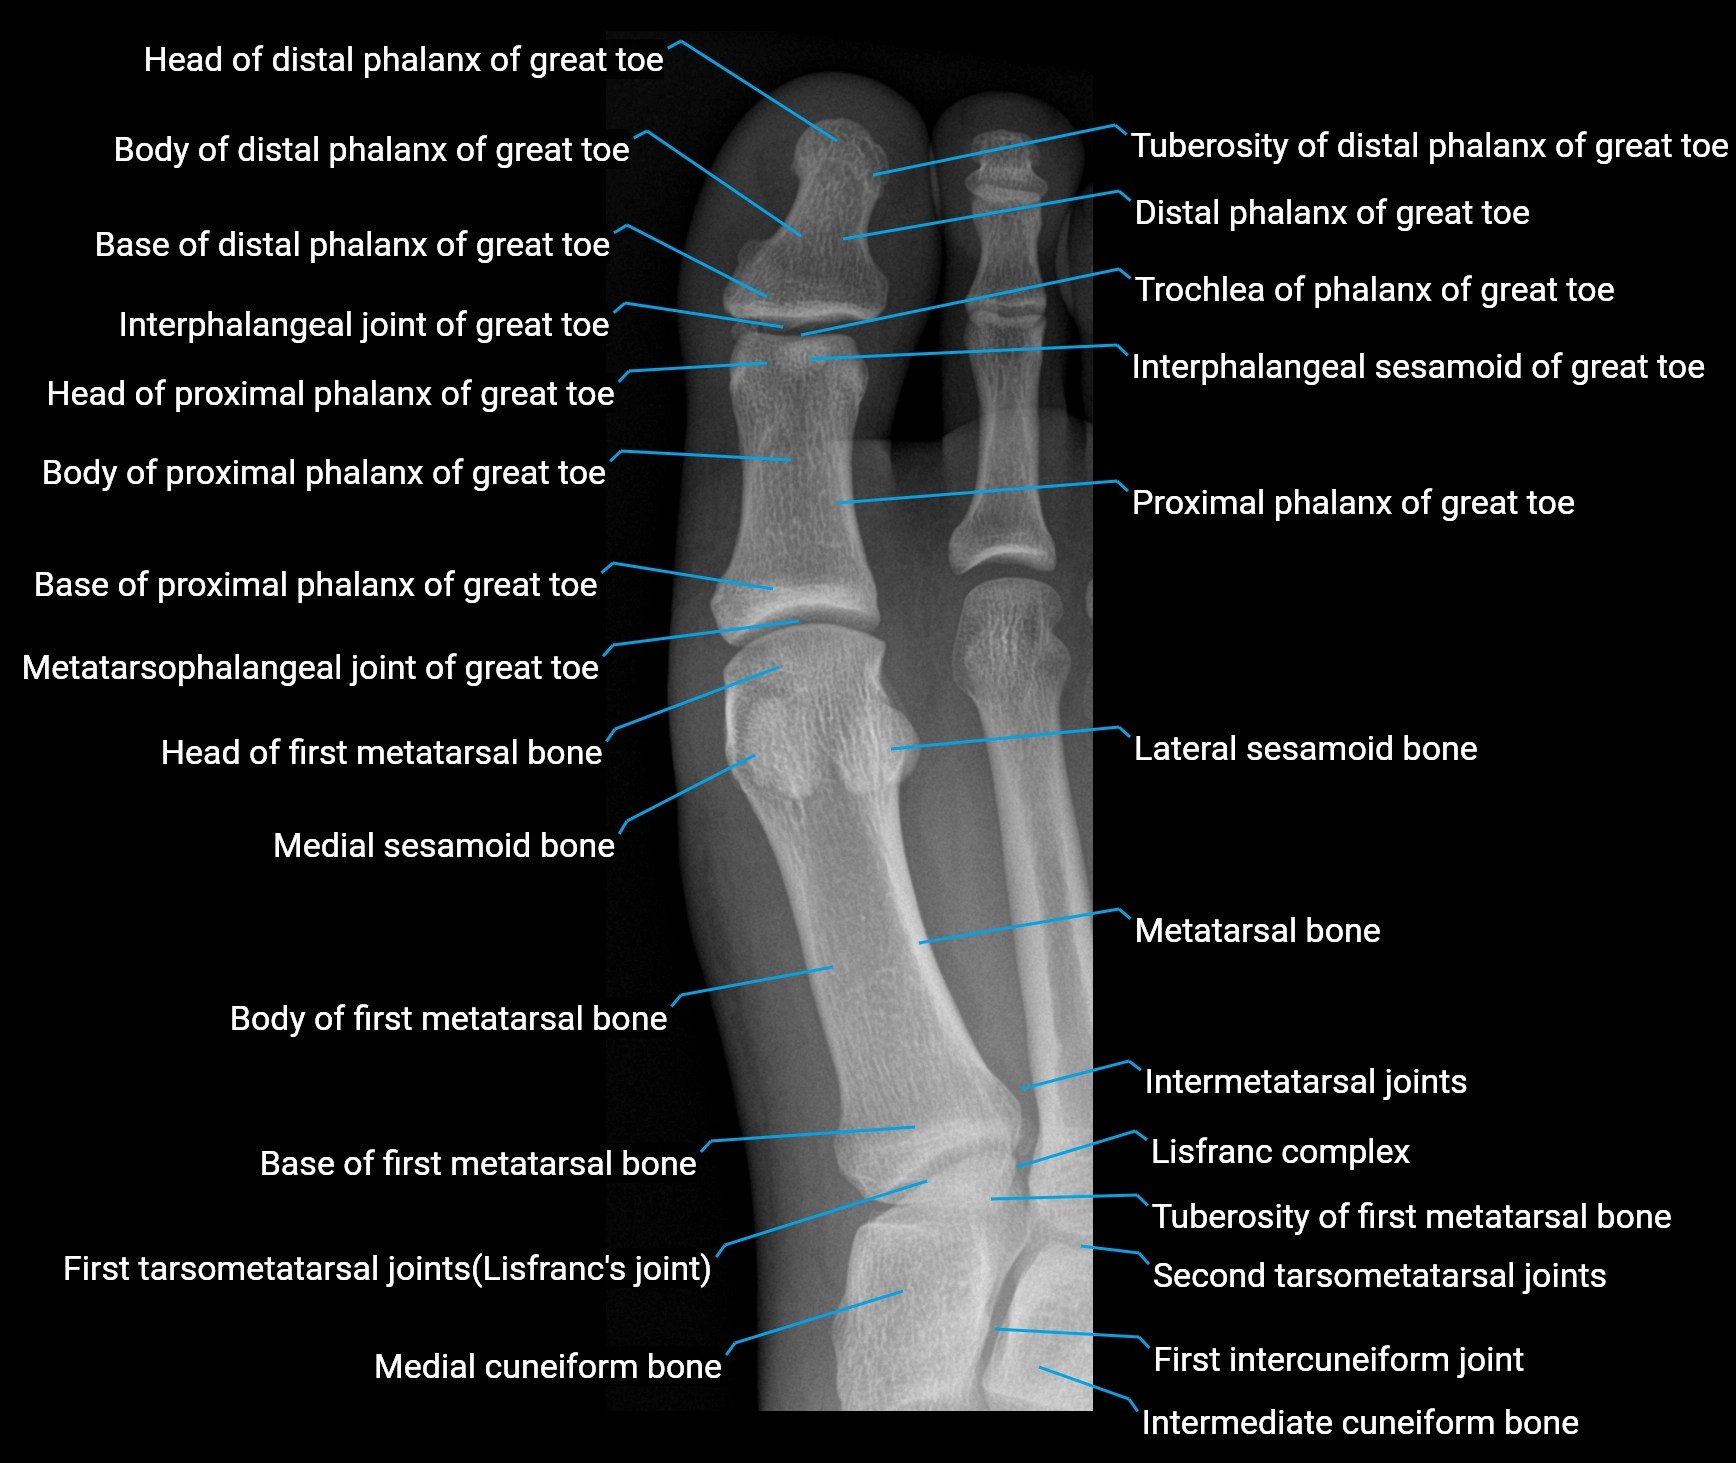

CT Appearance

Non-Contrast CT:

-

Muscle: homogeneous soft-tissue density lateral to calcaneus

Tendon: linear soft-tissue density running toward the fifth toe

Chronic changes: tendon thickening or calcification at its insertion on the fifth metatarsal

Subcutaneous fat: clearly outlines lateral tendon course